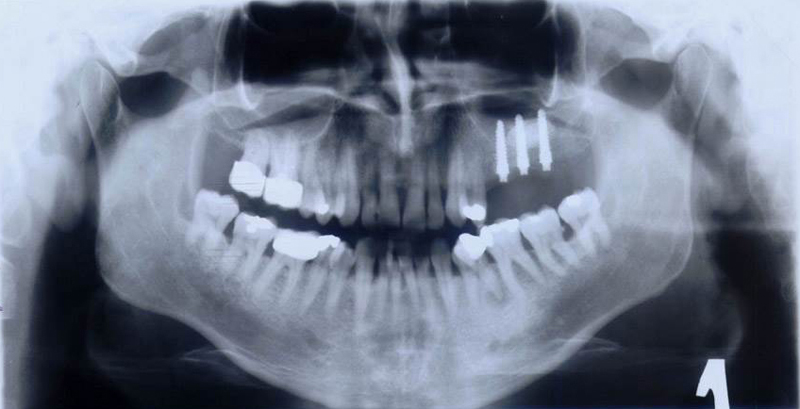

Při ztrátě molárů a premolárů v horní čelisti a jejich náhradě implantáty se často setkáváme s nedostatečnou

vertikální nabídkou kosti pod čelistní dutinou, často doprovázenou i nedostatečnou horizontální nabídkou a sníženou kvalitou kosti (v oblasti 2. premoláru v 50%, v oblasti moláru až v 80% případů nedostatečná kostní nabídka)

Od roku 1985 je tento problém řešen augmentační operací nazývanou

sinus lift.